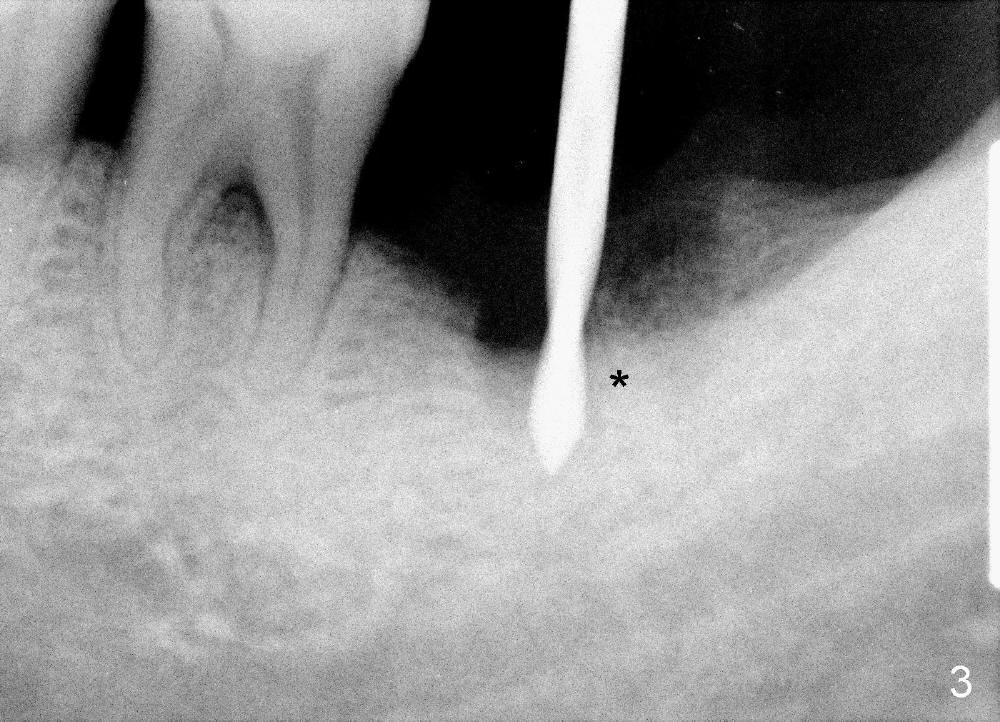

A 51-year-old man has generalized chronic periodontitis. The mesial root of #18 has vertical fracture (Fig.1*) with infection. The patient agrees extraction (Fig.2) and immediate implant. The septum is thin. The pilot drill drops into either the mesial (Fig.3) or distal sockets. Furthermore it is difficult to control pain probably due to severe infection (Fig.2 >: mesiobuccal erythema and edema). Repeated local infiltration does not alleviate pain associated with drilling. Block anesthesia has to be administered (one carpule of 2% Lidocaine with 1:100,000 Epinephrine). Damage to the inferior alveolar nerve (Fig.1 red dashed line) increases. On the other hand, osteotomy through the socket of the tooth with periodontits is easier because of shallow socket. Retraction of the buccal gingiva can reveal the bottom of the socket. We will increase the depth slowly until a tap obtains initial stability. The worst scenario is that active hemorrhage from the socket bottom is encountered initially. The nerve injury can be reduced minimally.

Now where to initiate osteotomy? Since the mesial crest is much lower than the distal (compare arrowheads in Fig.1), placement of an implant in the mesial socket is a good approach, whereas placement in the distal socket is not good for restoration (cantilever). The thin septum is slippery to drill penetration. What should we do?